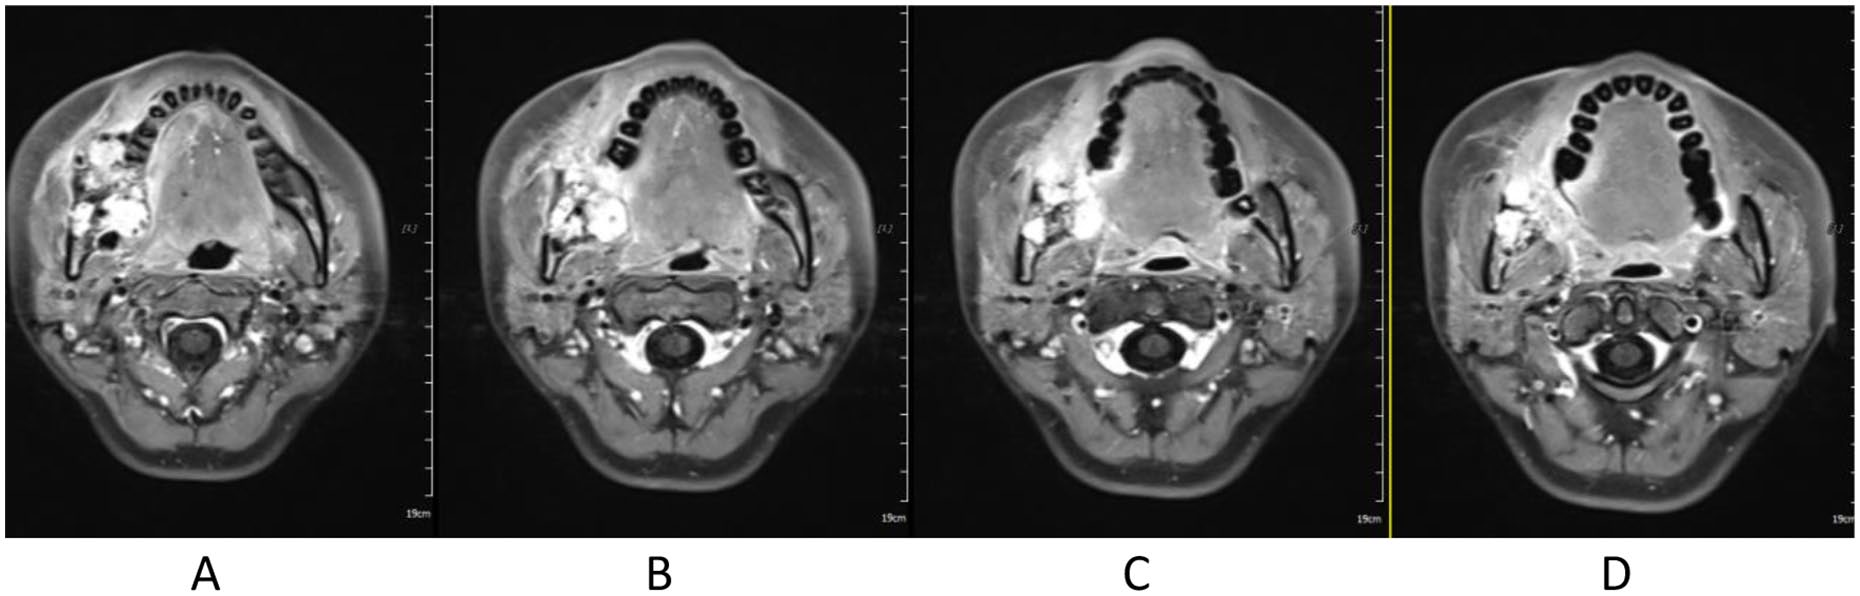

Treatment was tolerated well. During and after CIRT, there was only grade 2 skin (Figure 2) and oral mucosa acute adverse event, and no grade ⩾3 RTOG acute effect. During and after CIRT, her pain in the right mandible is continued but never aggravated, but painkiller is not needed; 6-month post completion of radiotherapy, she was in a very good clinical state, and the pain in the right mandible resolved completely. One to three months after CIRT, there were no significant changes of tumor size on MRI (Figures 3–6), just intensity of contract enhancement gradually diminished on contract-enhanced T1-weighted MRI; from 6months on, the size of the tumor decreased gradually (Figure 7); up to 16months after CIRT, it regressed to 3.6cm×3.2cm×1.7cm; and on 19months after CIRT, it regressed to 3.6cm×3.2cm×1.7cm, and the efficacy evaluation is PR (partial response) (Figures 8–10).

Figure 5. 1 month after CIRT.

Figure 6. 3 months after CIRT.